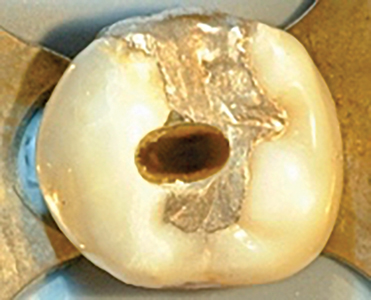

Many of our patients are attracted to the allure of cheaper dental treatment abroad. Tooth #36 in the accompanying radiograph (Fig. 1) and photo (Fig. 2) is an example of such a case. Unfortunately in this case, almost every possible iatrogenic endodontic mishap was encountered. This treatment is substandard and if done in Canada the … Read more